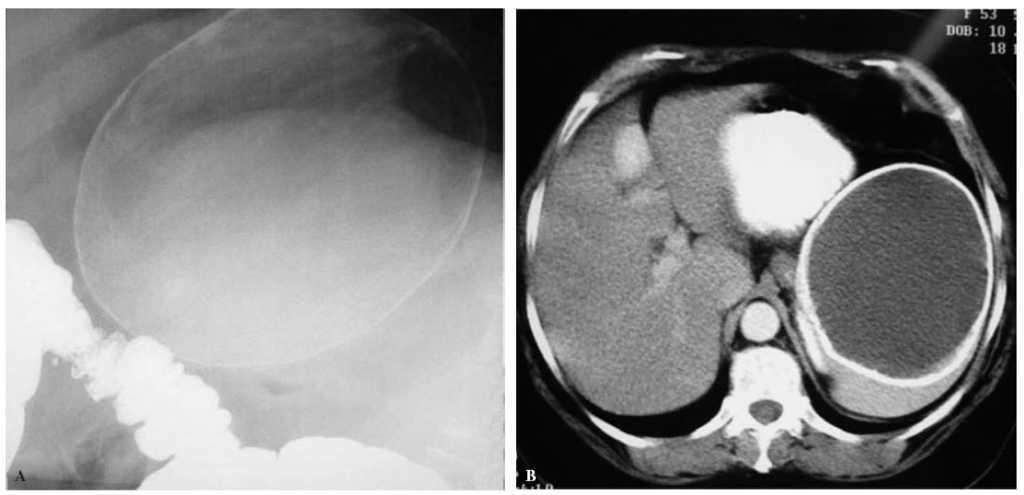

Fig.1.A:imagen de enema opaco en la que se observa la masa quística calcificada sin relación con el colon.B:corte de tomografía com-putarizada:quiste esplénico de 13 µ20 cm calcificado en su totalidad.

Caso clínico: mujer de 54 años, colecistectomizada 30 años antes. Hallazgo casual en radiografía simple de masa quística calcificada en el hipocondrio izquierdo. Asintomática, exploración y analítica normales (serología hidatídica negativa). Ecografía y tomografía computarizada (TC): masa quística en hipocondrio izquierdo, pared calcificada, bien delimitada de 13 µ20 cm; enema opaco: sin relación con la luz intestinal. Intervención: QE de consistencia pétrea adherido a hígado, estómago y diafragma que imposibilitó la preservación del bazo; se realizó esplenectomía. Postoperatorio normal. Estudio anatomopatológico: formación quística unilocular, pared lisa, grosor de 2-3 cm y apariencia de calcificación; al microscopio se observa constituida por tejido fibroso con depósito cálcico en su totalidad, sin revestimiento epitelial.